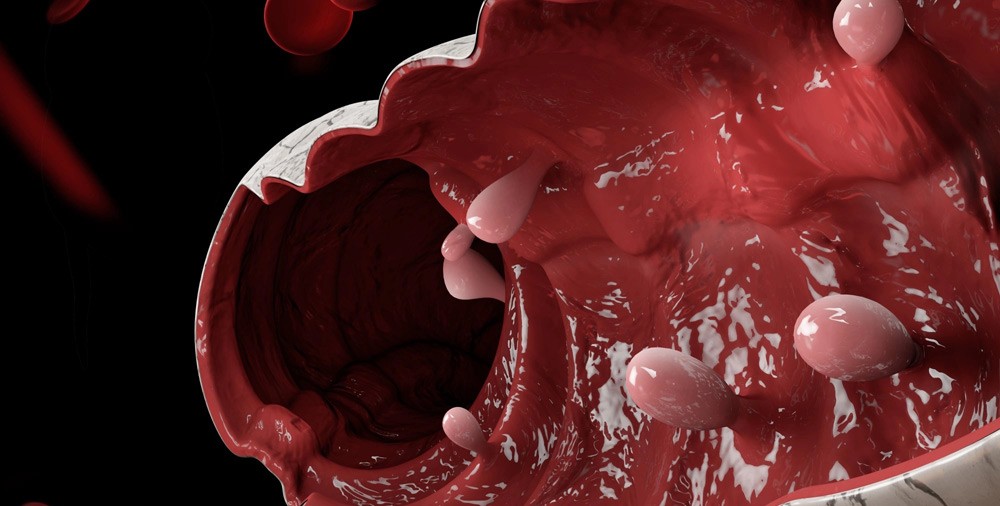

Поліпи — це тихі гості на слизовій оболонці органів, ніби неслухняні кущики, що випинаються з поверхні, ніби намагаються привернути увагу. Зазвичай вони доброякісні, але в деяких випадках перетворюються на серйозну загрозу, особливо якщо їх ігнорувати. Найчастіше трапляються в кишечнику, матці чи носі, де слизова постійно стикається з подразниками — їжею, гормонами чи інфекціями.

Уявіть тонку плівку слизової, яка раптом починає розростатися: від міліметрових крапельок до великих наростів на ніжці чи широкій основі. За даними медичних оглядів, у людей старше 50 років поліпи кишечника виявляють у 20–50% випадків під час скринінгу. Вони не болять одразу, але можуть кровоточити чи блокувати прохід, сигналізуючи про себе червоними слідами в калі чи нестерпним дискомфортом.

Товста кишка — фаворит для поліпів, особливо після 50. Вони ростуть роками, ніби повільні дерева в саду, і часто безшумно. У 73% випадків локалізуються в лівій половині кишки, де ризик раку вищий. Симптоми прокидаються пізно: червона кров у калі, як несподіваний гість на білих простирадлах, запори чи діарея, що чергуються, біль ниючого характеру.